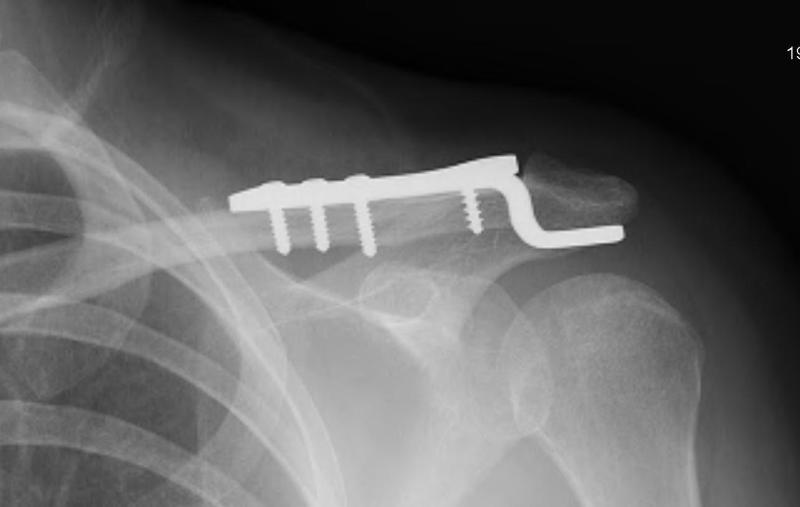

# تدبير كسور منتصف عظم الترقوة: دليل شامل تُعتبر كسور منتصف عظم الترقوة من الإصابات الشائعة نسبيًا، وتمثل تحديًا علاجيًا ي…